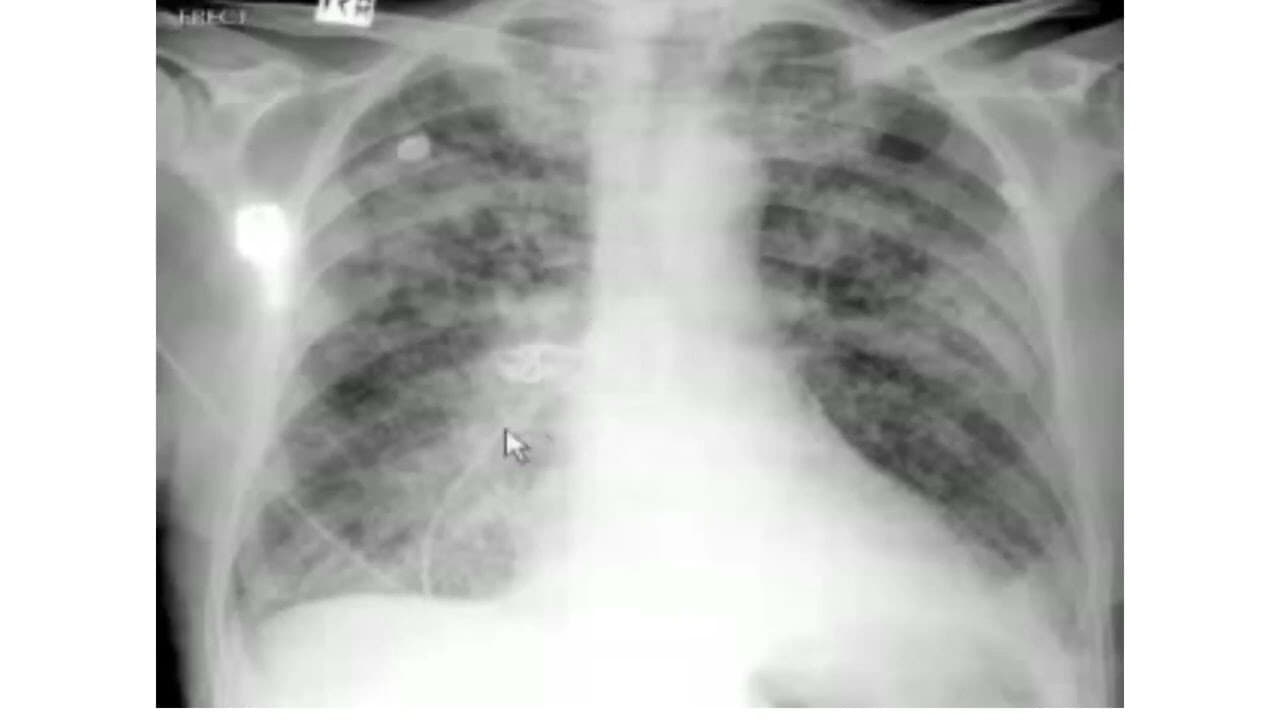

Pulmonary edema: X-Ray review

in this chest x ray review, we have explained general features of pulmonary edema and differentiated between normal and abnormal chest x ray. The chest X-ray or #CXR is still the most practicable and useful way to assess and quantify #pulmonary #edema radiologically. Features useful for broadly assessing pulmonary oedema on a plain chest radiograph include: upper lobe pulmonary venous diversion (stag's antler sign) increased cardiothoracic ratio/cardiac silhouette size: useful for assessing for...